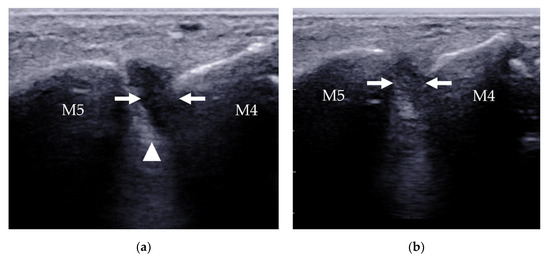

| Plantar plate tear | 2nd MTP joint | discrete anechoic cleft or area of heterogeneous echotexture in the plantar plate |